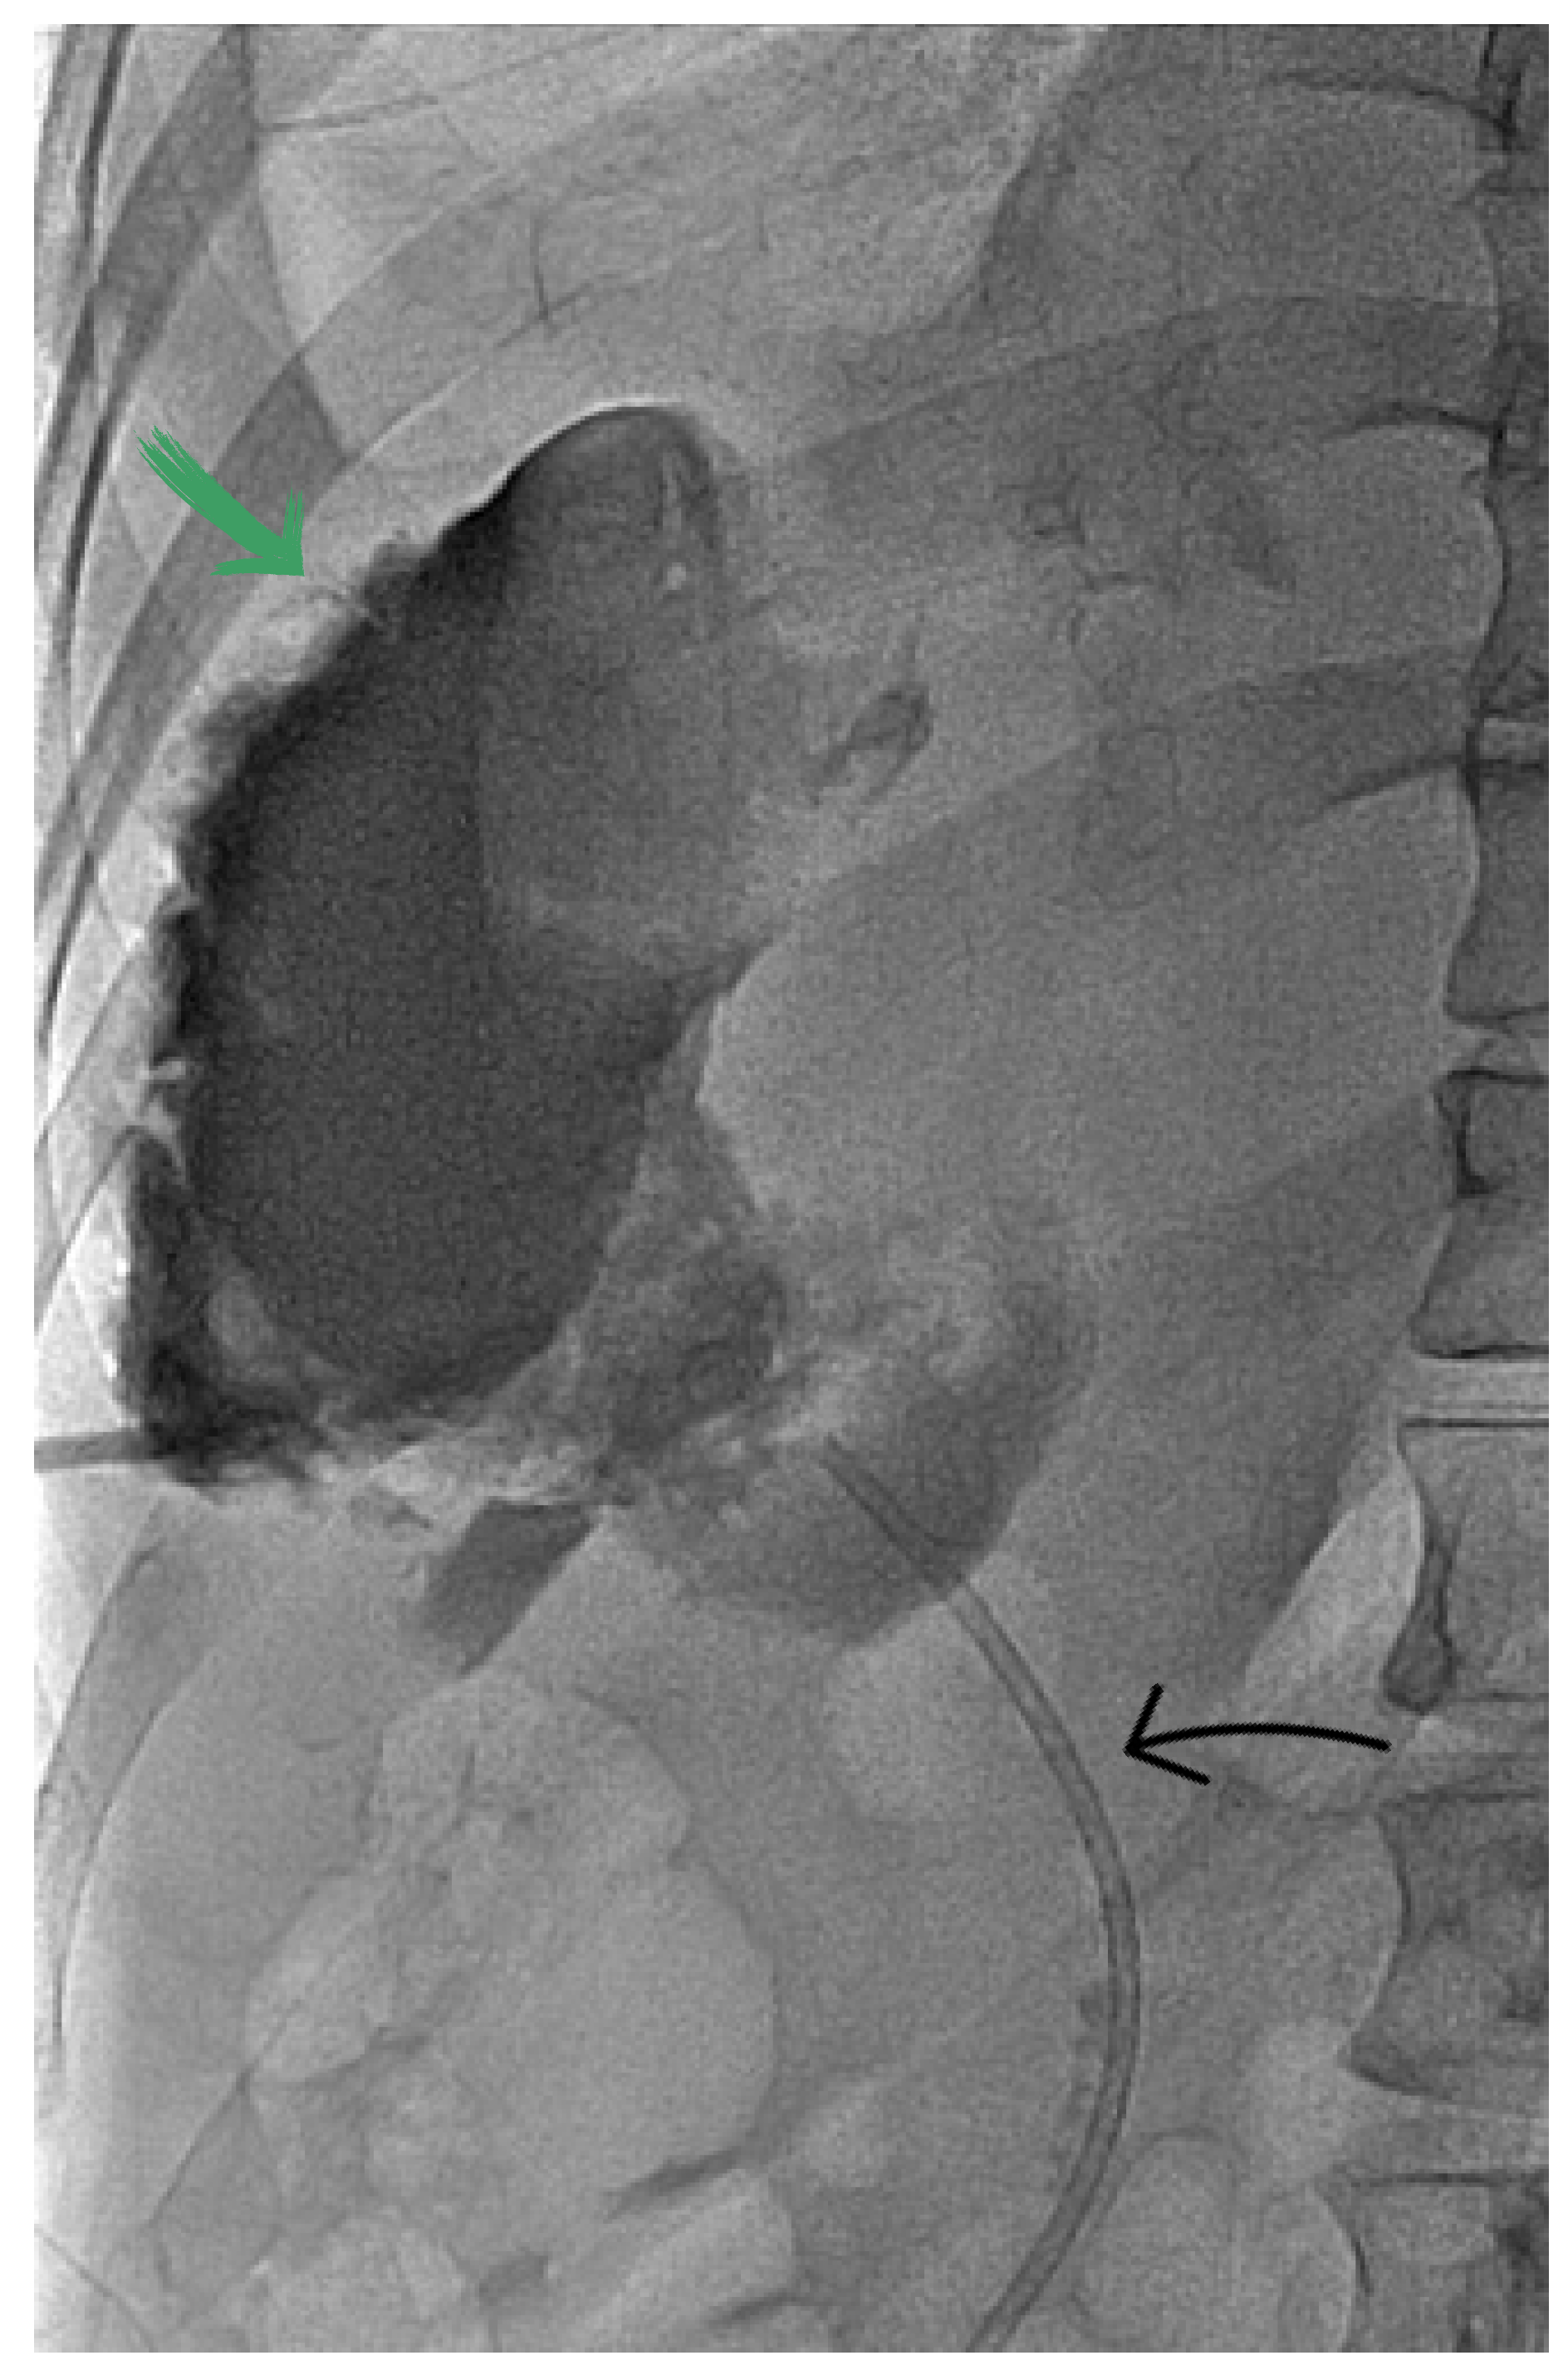

2. Case Report